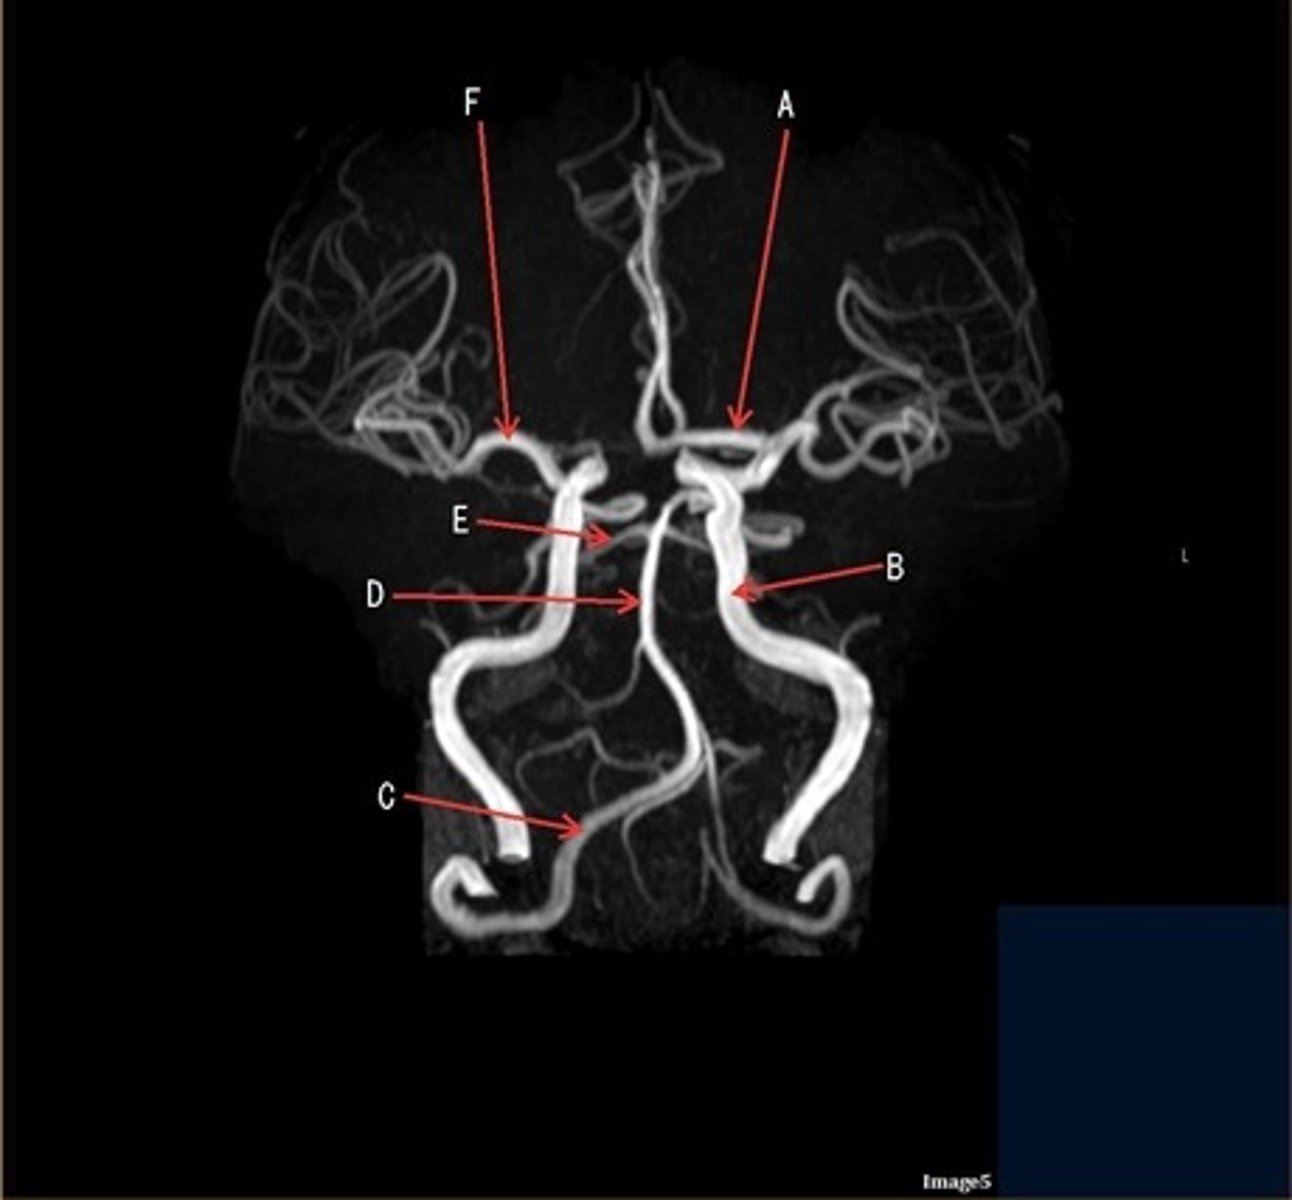

A

A- anterior cerebral artery

B

B- internal carotid artery

C

c- vertebral artery

D

D- basilar artery

E

E- posterior cerebral artery

F

F- middle cerebral artery

Which arteries join together to form the basilar artery?

vertebral arteries

letter A

anterior cerebral artery